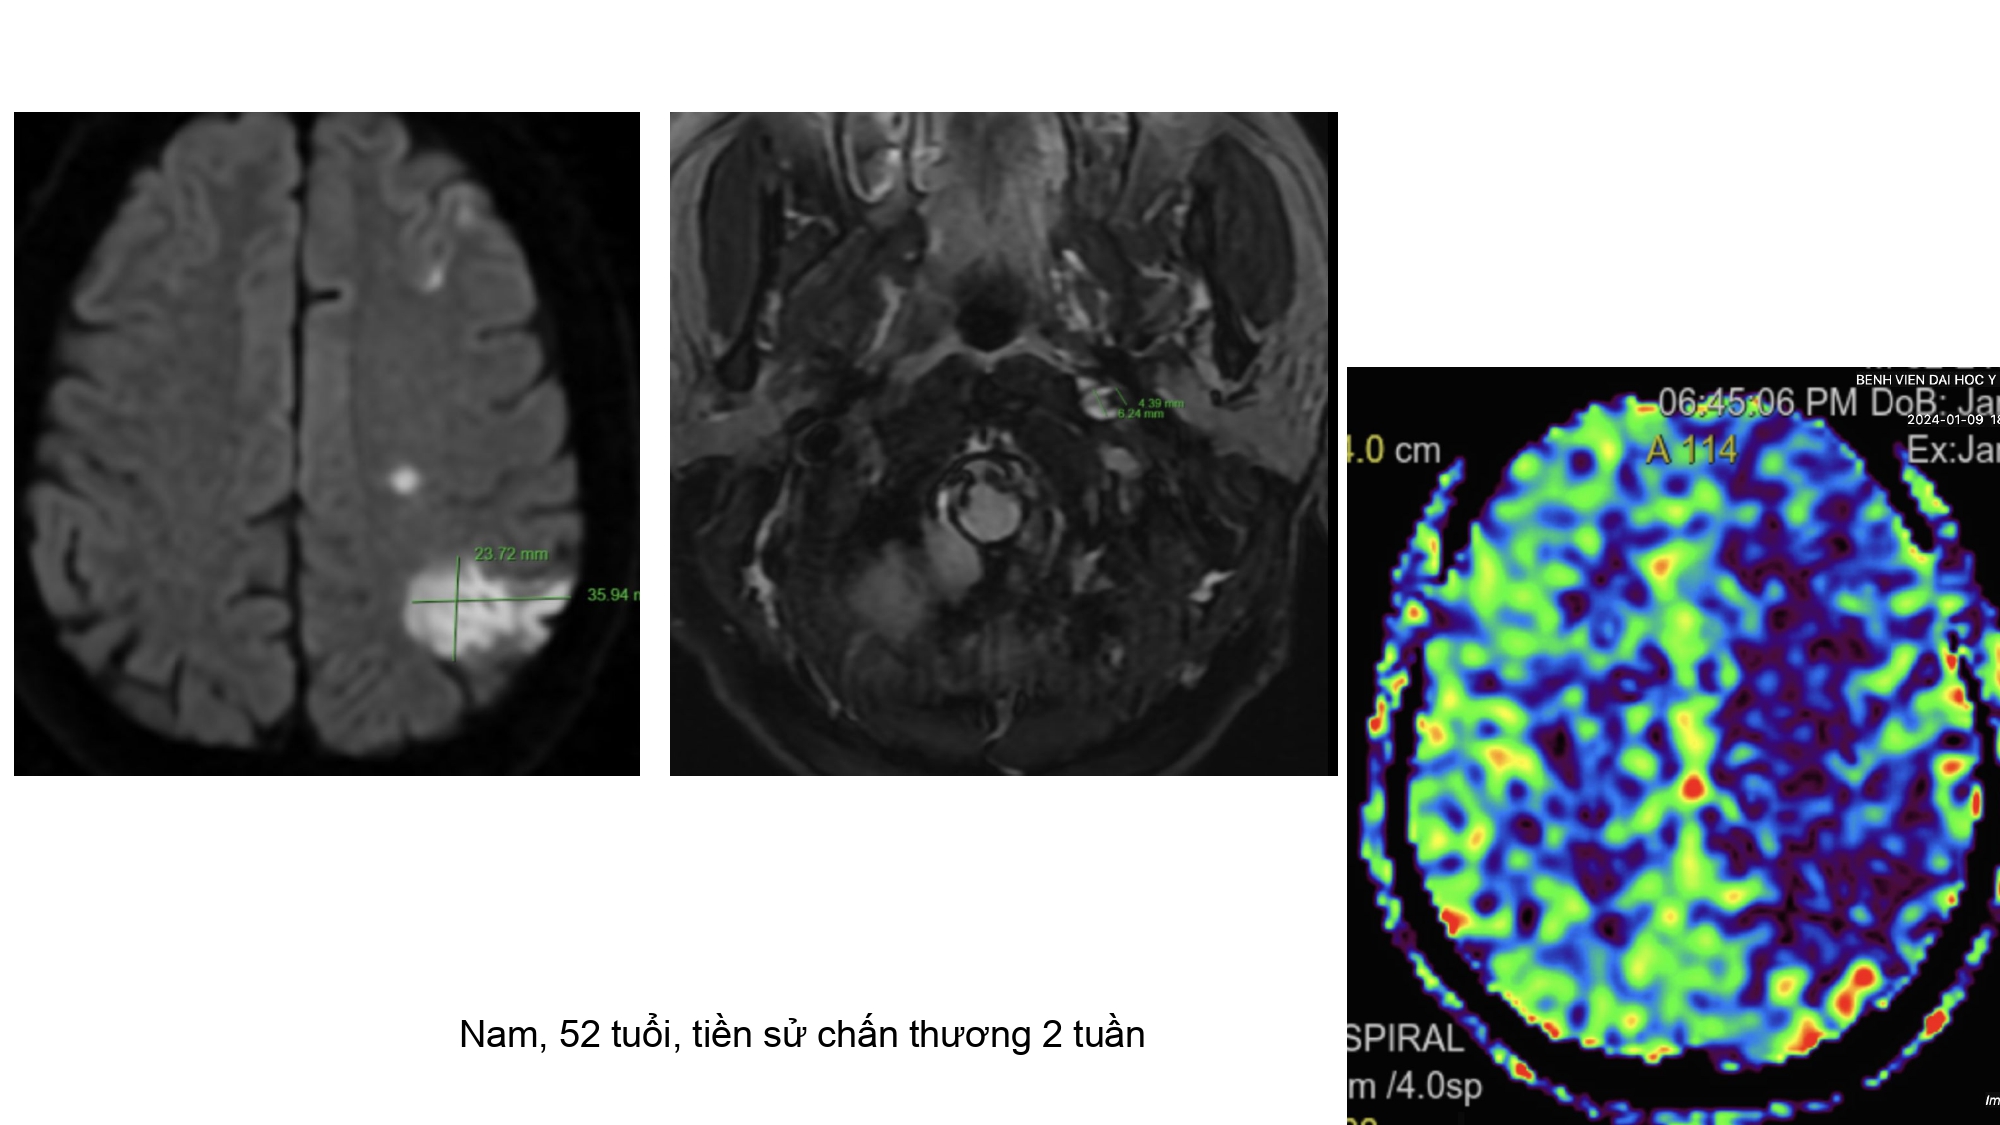

| 14:10 - 15:10 | DEBATE 2 | Recurrent chronic subdural hematoma– surgical or endovascular intervention? Surgical: Assoc. Prof. Duong Dai Ha Endovascular: Assoc. Prof. Le Thanh Dung | Moderator: Prof. Christian Matula Assoc. Prof. Duong Dai Ha | |

| 15:10 - 16:10 | Interactive Case Demonstration and Discussion II: ~20 minutes each, (5 minutes presentation followed by 15 minutes discussion) Practicals: How I am doing it? Participants present case presentations about how they do it? The faculty comment on and discussion. 1. Endoscopic approach in post-traumatic CSF leakage - Dr. Nguyen Thanh Xuan 2. Endovascular approach in CCF - Assoc. Prof. Le Thanh Dung | Prof. Christian Matula International & local faculties Participants | |